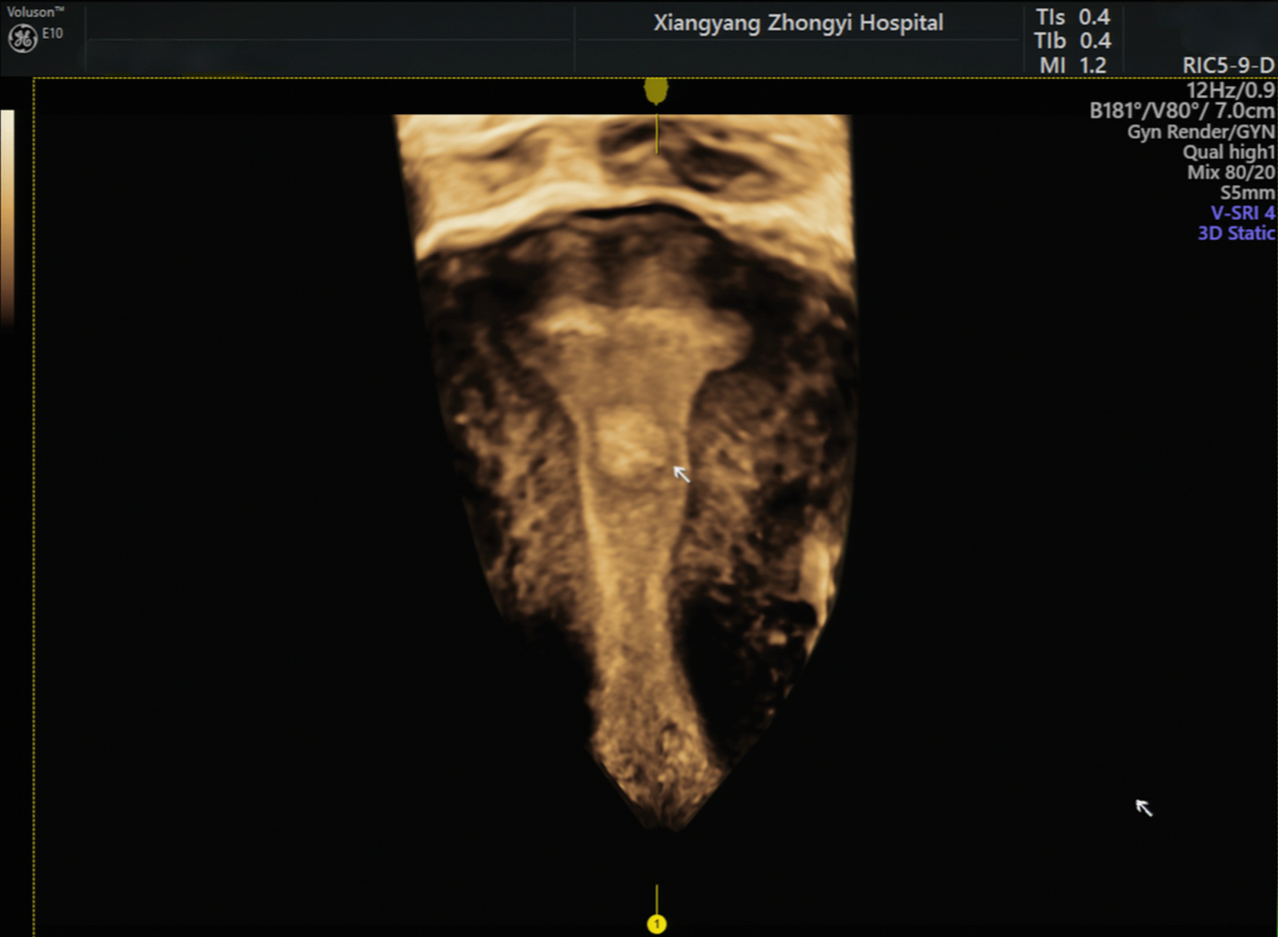

该院妇科副主任江晓婧接诊了李女士,在详细询问病史及体格检查后,为其开具了经阴道超声检查。超声医学科医师胡晓丹为李女士进行了二维彩超检查,结果发现宫腔内见一高回声区、边界清晰、回声均匀,为了进一步明确病灶位置、形态等,张晓燕在与李女士沟通并取得同意后,采用宫腔三维彩超进行检查,清晰地观察到宫腔左侧中上段有一个约1.8cm*0.9cm*1.2cm的团块样回声,考虑为子宫内膜息肉,为妇科医疗团队提供宫腔镜手术“路线图”。

超声医学科主任施唯介绍,子宫内膜息肉是子宫腔内局部内膜过度生长形成的良性赘生物,大小从几毫米到几厘米不等,其表现多为子宫出血、不规则月经、中老年人可出现绝经后出血,部分患者可能有下腹隐痛、白带异常,甚至还可能影响胚胎着床。子宫内膜息肉约三分之一患者可能没有任何症状,仅在体检行经阴道超声时偶然发现,经阴道超声,是首选的筛查方法。常规经阴道二维超声可发现息肉,但宫腔三维超声能立体成像、清晰显示息肉的大小、数量、位置等,为宫腔镜手术精准定位、完整切除提供精准依据。